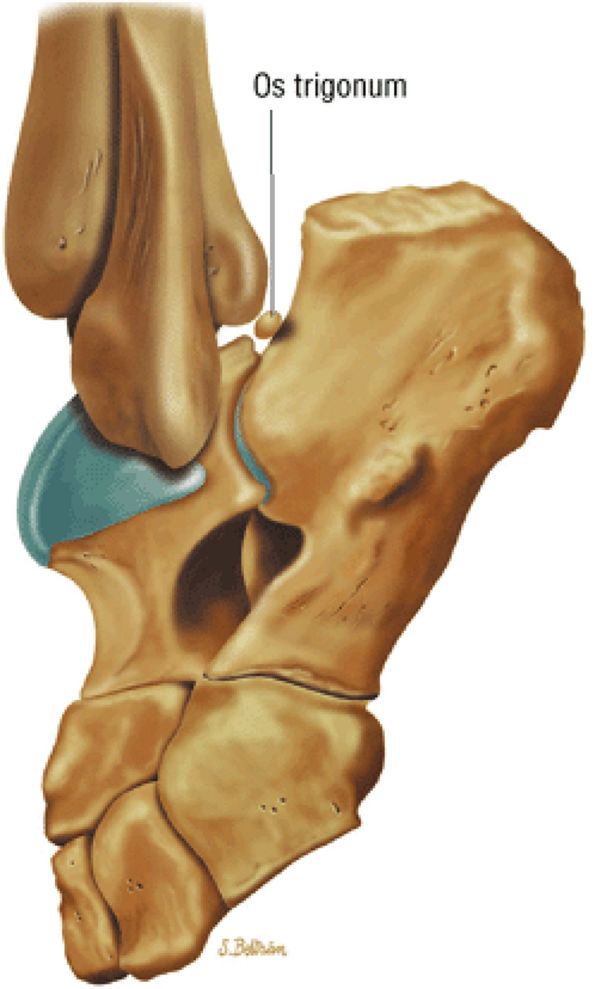

hyperintensity on T1-weighted images, secondary to fatty marrow. This finding should not be mistaken for tendon degeneration or a tear. Accessory bones, including the os tibiale externum (an accessory navicular bone medial to the navicular) and the os trigonum (located posterior to the talus and occurring approximately 10% of the time), represent commonly seen secondary ossification centers. These are normal variants that may be misinterpreted as a fracture or loose body.21

FIGURE 5.25 ● Sagittal anatomy of the ankle and foot. (A) The origins of the anterior talofibular ligament and posterior talofibular ligament are identified arising from the anterior and posterior distal tip of the lateral malleolus. From the origin, the full course of these ligaments can be followed medially on successive sagittal images to their insertions on the anterior and posterior talus. (B) The vertical course of a long segment of the peroneus longus and brevis tendons is often visualized on a single sagittal image through the tendons. This image is useful to further characterize tendinosis and longitudinal tears or splits, and for measuring the gap between completely ruptured tendon fragments. (C) The anterior process of the calcaneus is a common location for fractures that are occult on plain film. They are optimally visualized in the sagittal plane on MR exams. (D) In addition to occurring at the tibiotalar joint, degenerative arthrosis is also commonly found at the posterior subtalar, calcaneocuboid, and talonavicular joints. The cartilage surfaces and subchondral bone at these articulations are optimally visualized in the sagittal plane. (E) The presence of an os trigonum posterior to the talus predisposes certain athletes with a predilection for plantarflexion to the os trigonum syndrome. This is diagnosed on sagittal MR images when edema is visualized within the os trigonum and extends across the synchondrosis into the posterior talus. (F) Abnormal signal in the sinus tarsi manifests as high signal on FS fluid-weighted sequences and low signal on non-FS sequences. This abnormal signal may suggest, but is not specific for, inflammation in the sinus tarsi. Other causes of abnormal signal in the sinus tarsi, which may be incidental and asymptomatic, include extension of joint fluid from the posterior and middle subtalar joints, extension of generalized edema throughout the soft tissues of the ankle from stasis or other causes, enlarged vessels, and ganglion cysts.(G) Two potential causes of an incidental “mass” palpated on physical examination about the Achilles tendon are a low-lying soleus muscle and an accessory soleus muscle, both of which are diagnosed by MR imaging. The normal soleus muscle extends to about the proximal one third or one half of the Achilles tendon. A low-lying soleus will extend to the distal third of the tendon. An accessory soleus is present when there is an extra muscle in the pre-Achilles fat, usually extending to the distal third of the tendon, often near the distal insertion. (H) In the setting of a complete Achilles tendon rupture, the location of the tear may be at the myotendinous junction, mid-tendon, distal tendon, or tendon insertion at the os calcis. In addition, the tear is characterized as transverse or oblique longitudinal. In the case of transverse tears, the distance between the tear and tendinous insertion at the calcaneus is measured. Also, the length of good-quality tendon stump at the calcaneal insertion is measured, since the surgeon often uses the distal stump in the surgical reconstruction or repair. (I) The anteromedial aspect of the tibiotalar joint is a common location for the formation of large osteophytes, which extend anteriorly from the anteromedial tibia and talus. These may cause pain, limit the range of motion, or break off and form loose bodies within the tibiotalar joint. This spectrum of findings is part of the anteromedial impingement syndrome. (J) Ancillary findings at the plantar aponeurosis visualized on sagittal images include bone marrow edema within the inferior calcaneus, inferior calcaneal enthesophyte with marrow edema, and high signal within the flexor digitorum brevis muscle and fat that surround the plantar aponeurosis. These findings suggest active inflammation in the tissues surrounding the plantar aponeurosis. (K) The deltoid ligament is found on sagittal images by finding its origin extending off the bilobed medial malleolus. The medial course of the deltoid ligament components is followed over the next two or three successive sagittal images. (L) The vertical course of the tibialis posterior tendon and the flexor digitorum longus tendon is often visualized on a single image. Triangulating on tendon pathology in both the sagittal and axial planes aids in further characterizing tendon abnormalities.